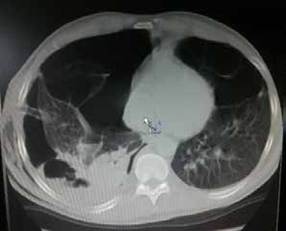

En el leucograma del momento del derrame pleural se encontró: leucocitosis con predominio de los polimorfonucleares (leucocitos: 12,6 x 109/L; polimorfonucleares: 85,9 %). Se decidió practicar una pleurotomía mínima baja, añadiendo otro antibiótico y manteniendo la terapia respiratoria, medidas que contribuyeron a la mejoría de la sintomatología. Posteriormente, al pinzar los drenajes torácicos, el pulmón se colapsó nuevamente, por lo que se le hizo una tomografía computarizada (TC). Se observó escaso parénquima pulmonar con múltiples bullas de diferente tamaño diseminadas en ambos campos pulmones, algunas de ellas con niveles hidroaéreos en su interior en la base del hemitórax derecho; también, había moderado colapso pulmonar derecho (figura 2).

Figura 2. Tomografía computarizada de tórax en la que se observa escaso parénquima pulmonar, con múltiples bullas de diferentes tamaños localizadas en ambos campos pulmones, algunas de ellas con niveles hidroaéreos en su interior en la base del hemitórax derecho. También, se observa moderado colapso pulmonar derecho.